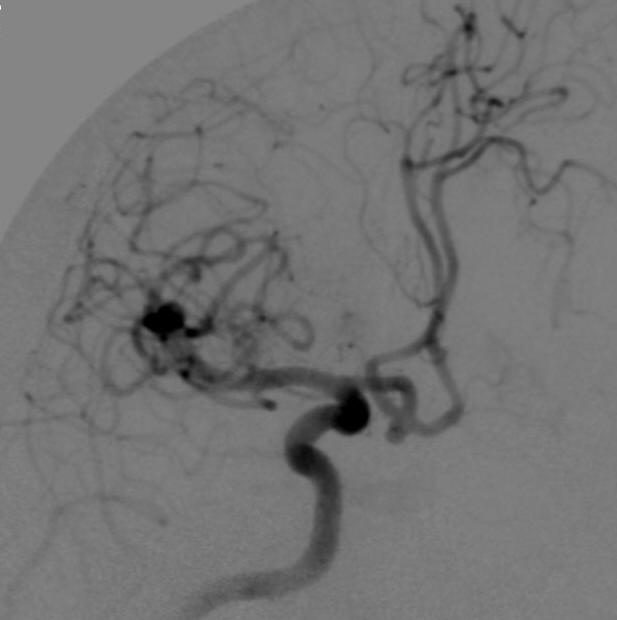

病例2